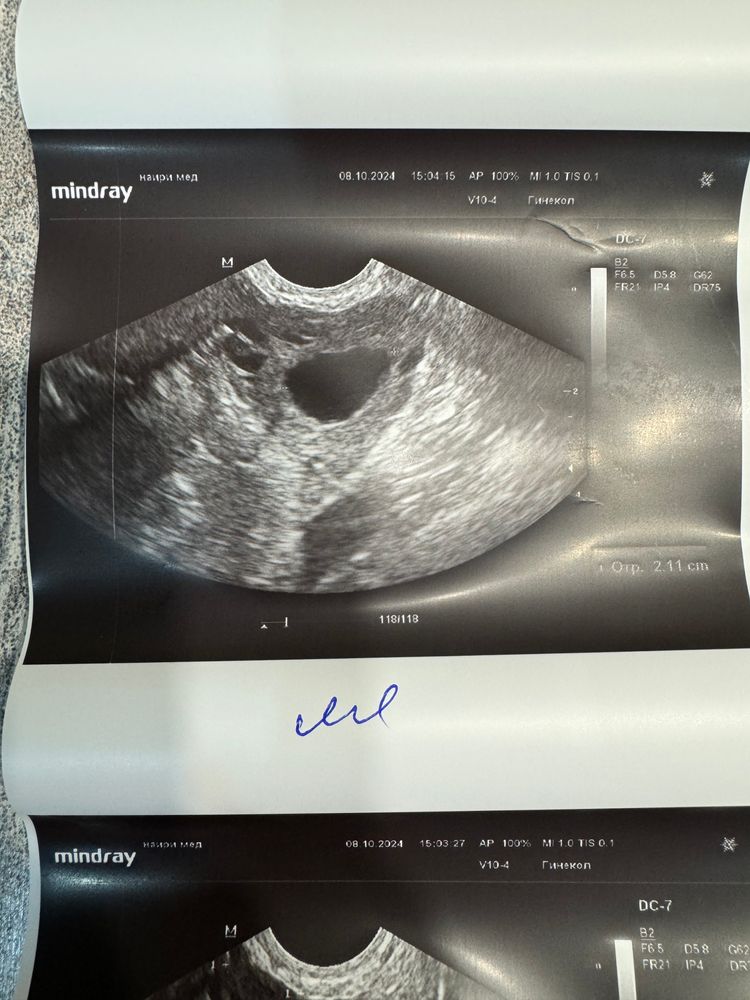

Была на УЗИ сейчас: в левом яичнике фолликул 21 мм. Узист говорит, что сегодня-завтра может быть овуляция. Но эндометрий 5,5 всего( Нет смысла пытаться?